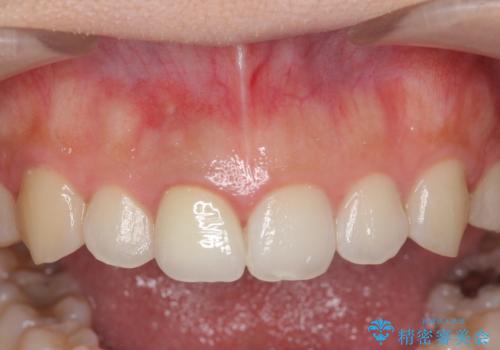

歯ぐきにできものができた 前歯の色調改善

- 歯ぐきに、にきびのようなものができ治らない、と治療を希望され来院されました。

歯髄の検査、X線検査より神経の失活が確認されたので、根管治療・ファイバーコア築盛 ・ジルコニアクラウンの製作、と治療を進めます。